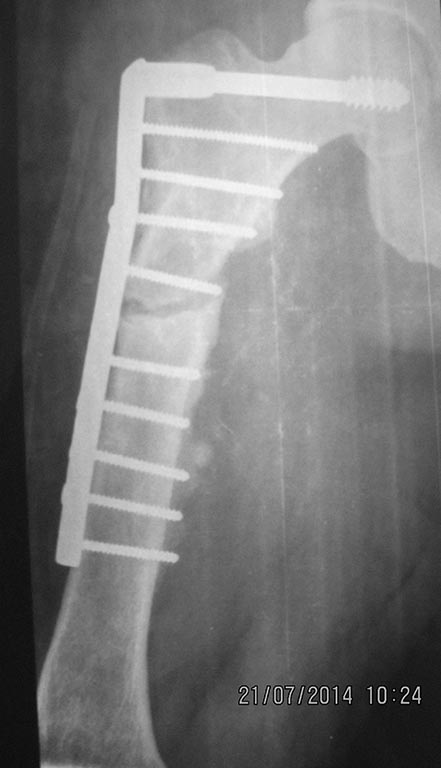

[Ortho] перелом бедра с исходной деформацией

Выкладываю, как и обещал. За репозицию педплечья не осуждайте!